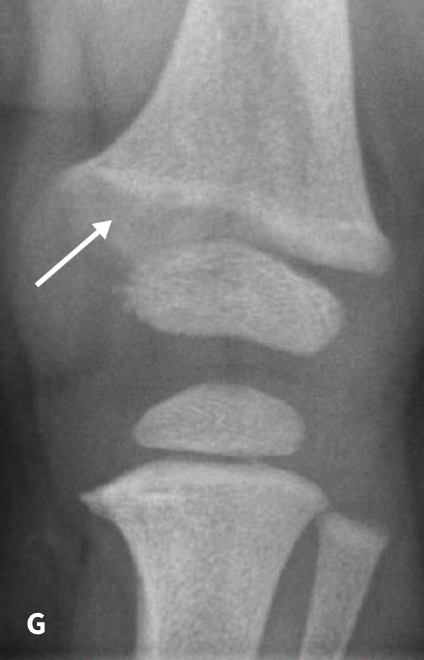

The RSS is a quantitative method that uses radiographs to assess the severity of rickets at the wrists and knees. Originally validated in nutritional rickets, the score is based on the degree of metaphyseal fraying, metaphyseal cupping, and the proportion of the growth plate that is affected. It is a 10-point scale, for which 10 represents the most severe radiographic changes due to rickets and 0 represents the absence of these changes.1

Although the severity and duration of rickets vary considerably between XLH and nutritional rickets, the radiographic features of rickets at the growth plate are similar in the two disorders, which allowed validation of the RSS in XLH. The RSS correlates with serum alkaline phosphatase (ALP) levels, a biochemical marker of rachitic activity, and this scoring system can be used to assess the radiographic response following treatment of nutritional or XLH rickets.

The RSS in XLH has been reported to range from 0 to 4.5; however, despite the smaller RSS range observed in XLH patients, inter- and intra-rater reliability are similar to those reported for nutritional rickets. Patients with XLH who had a baseline RSS ≥1.5 were shown to have more severe hypophosphatemic bone disease, including higher levels of alkaline phosphatase, and greater impairments in clinical outcomes compared with patients who had a baseline RSS <1.5.